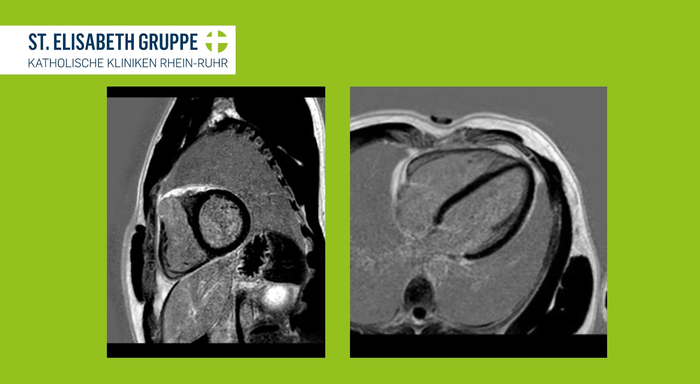

Die Herz-MRT (Kardio-MRT)

Für die „funktionelle“ Diagnostik des Herzens wird in der Radiologie die kardiale Magnetresonanztomographie (Herz-MRT) eingesetzt. Die Herz-MRT ist neben der Herz-CT ein weiteres wichtiges, nicht-invasives bildgebendes Verfahren, das eine wertvolle Sicht auf das schlagende Herz, seine Funktion und unterschiedliche Gewebe geben kann. Es liefert den Herzspezialisten aufschlussreiche und therapie-entscheidenden Einblicke. Im Gegensatz zum Herz-CT erfolgt die Herz-MRT nicht mit Röntgenstrahlung, sondern mit Magnetfeldern und geringen Mengen an MRT-Kontrastmittel. Das Verfahren eignet sich unter anderem bei strukturellen und entzündlichen Herzmuskelerkrankungen sowie zur Herzinfarktdiagnostik.

Herz-MRT zur Beurteilung von Herzerkrankungen

Mit einer Herz-MRT können Gewebeeigenschaften, Funktionen und Durchblutung untersucht werden.